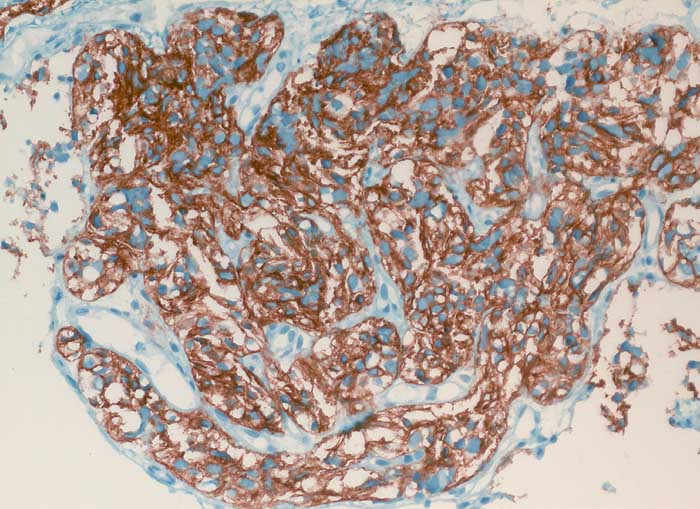

pit/ Typisches Karzinoid der Lunge

Typisches Karzinoid der Lunge

Die Diagnose hoch differenzierter neuroendokriner Tumoren ist schwierig, da ihre Oberfläche meist von Bronchialschleimhaut oder Bronchialepithel bedeckt ist und sie deswegen kaum Zellen abschilfern. Ausserdem sind die Atypien sehr diskret. Die Zellkerne sind rundlich bis oval, glatt begrenzt, fein granuliert und haben grosse Ähnlichkeit mit den Kernen von Flimmerzellen. Ohne Kenntnisse des klinischen Befundes sind Karzinoidzellen deshalb kaum von Basal- und Flimmerzellen zu unterscheiden. Der Zytoplasmasaum ist schmal und zerfällt leicht. Solche nackt liegenden Kerne können mit einem Lymphom verwechselt werden. Das typische Karzinoid hat eine sehr gute Prognose, kann aber in seltenen Fällen metastasieren. Die Unterscheidung von typischem und atypischem Karzinoid erfolgt am histologischen Schnitt durch Nachweis von Nekrosen und mehr als 3 bis 10 Mitosen pro HPF bei letzterem.